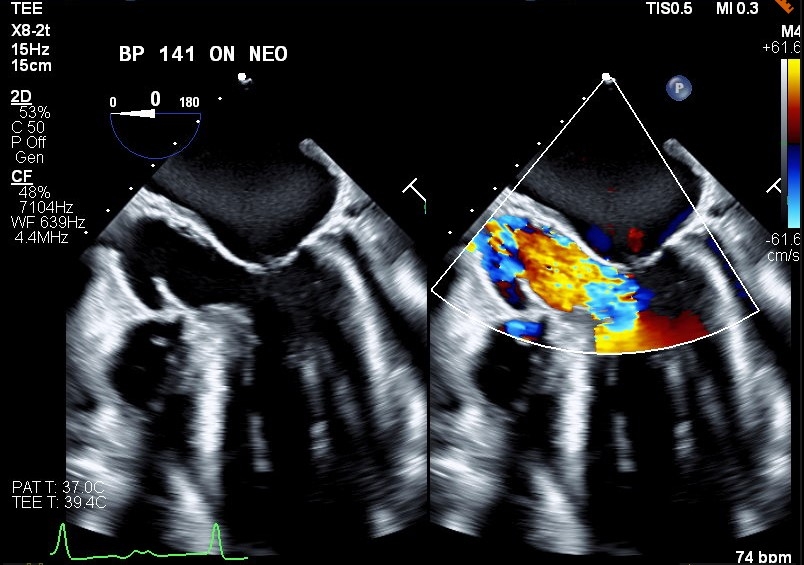

This case demonstrates classic cardiac physiology revealed in an unorthodox manner. Our patient is a 76-year-old male with a past medical history of HOCM, CAD, mild mitral regurgitation who presents to the hospital in the setting of chest pain. Work up revealed a high sensitivity troponin trend concerning for NSTEMI. Patient underwent a left heart cath where he was found to have a proximal LAD lesion with 99% stenosis requiring stenting. Post-intervention patient developed recurrent chest pain and a stat echocardiogram raised concerns for impending cardiogenic shock. Patient thus underwent emergent left and right heart cath. Impella LVAD placed for hemodynamic support. TEE was later obtained revealing moderate to severe mitral regurgitation, representing a progression from prior. At this time both advanced heart failure and structural heart service were consulted. The progression of the patient’s mitral regurgitation was thought to be impacting clinical deterioration and mitral valve transcatheter edge-to-edge repair (TEER) was discussed to address MR in the setting of obstruction. A multidisciplinary meeting resulted in decision to proceed with mitral valve TEER. Baseline hemodynamic gradients confirmed the presence of HOCM with peak-to-peak pressure gradient of 110 mmHg. Intraoperative TEE confirmed the presence of SAM and severe MR. The patient was prepared for a Pascal ACE clip, though in setting of this procedure phenylephrine was required for blood pressure support, revealing improvement in both SAM and MR. The patient was hemodynamically challenged with phenylephrine resulting in temporary resolution of MR and LVOT obstruction. These findings demonstrated a competent mitral valve with regurgitation resulting from HOCM physiology. After a multidisciplinary discussion, decision made to abort and withhold MV TEER.

This case demonstrates classic HOCM physiology in the setting of an attempted TEER procedure. With the addition of phenylephrine and increased afterload SAM resolved, as did much of the patient’s valvular regurgitation. This confirmed a competent mitral valve impacted by HOCM physiology rather than primary mitral valvular pathology. This case demonstrates the impact of structural imaging and competent imagers in the setting of complex anatomy and physiology. In this case TEE findings from provocative hemodynamic testing prevented unnecessary procedures.